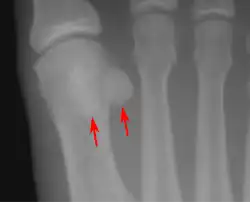

![]() Sesamoid bones at the distal end of the first metatarsal bone of the foot. | |

- In the foot—the first metatarsal bone usually has two sesamoid bones at its connection to the big toe (both within the tendon of flexor hallucis brevis).[10] One is found on the lateral side of the first metatarsal while the other is found on the medial side. In some people, only a single sesamoid is found on the first metatarsal bone.

- One or both of the sesamoid bones under the first metatarsophalangeal joint (of the great toe) can be multipartite – in two or three parts (mostly bipartite – in two parts).[12]

Lateral view.[11]

Bipartite medial sesamoid bone under the first metatarsophalangeal joint of the great toe of the left foot of an adult woman.